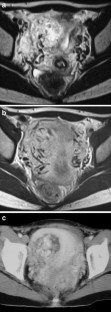

The endometrial cavity may demonstrate various imaging manifestations such as normal, reactive, inflammatory, and benign and malignant neoplasms. We evaluated usual and unusual magnetic resonance imaging (MRI) findings of the uterine endometrial cavity, and described the diagnostic clues to differential diagnoses. Surgically proven pathologies of the uterine endometrial cavity were evaluated retrospectively with pathologic correlation. The pathologies included benign endometrial neoplasms such as endometrial hyperplasia and polyp, malignant endometrial neoplasms such as endometrial carcinoma and carcinosarcoma, endometrial–myometrial neoplasm such as endometrial stromal sarcoma, pregnancy-related lesions in the endometrial cavity such as gestational trophoblastic diseases (hydatidiform mole, invasive mole and choriocarcinoma) and placental polyp, myometrial lesions simulating endometrial lesions such as submucosal leiomyoma and some adenomyosis, endometrial neoplasms simulating myometrial lesions such as adenomyomatous polyp and endometrial lesions arising in the hemicavity of a septate/bicornate uterus, and fluid collections in the uterine cavity (hydro/hemato/pyometra). It is important to recognize various imaging findings in these diseases, in order to make a correct preoperative diagnosis.